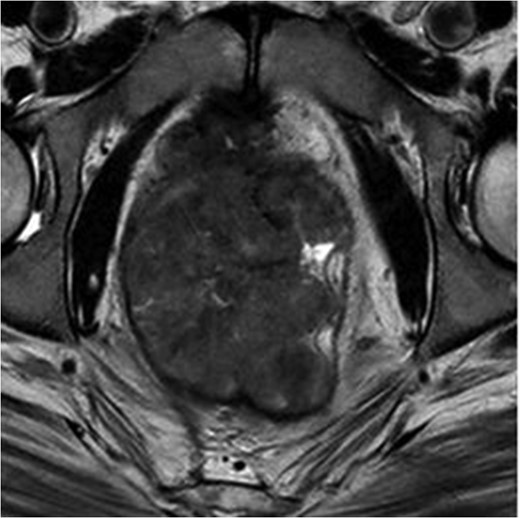

MRI pelvis. T2 axial image through pelvis demonstrating limited response to chemoradiotherapy with tumoral margins still predicted positive.